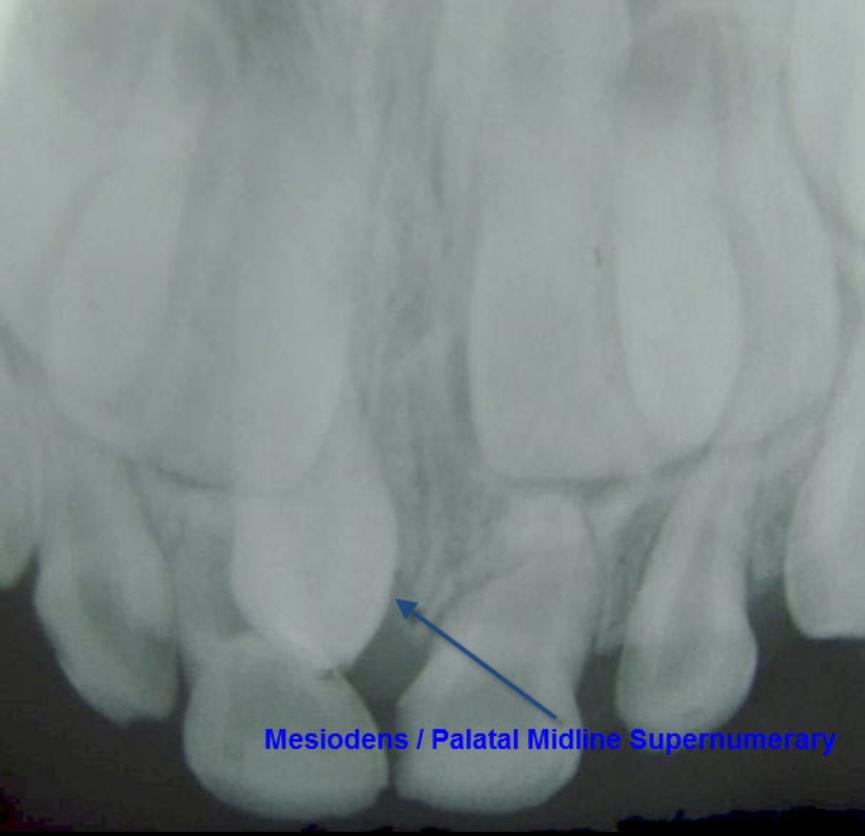

The prevalence of supernumerary teeth is reportedly between 0.15 – 3.9%. Most commonly, extra teeth are found between the upper central incisors (mesiodentes) or in the region of the premolars (paramolars) or very occasionally, behind the wisdom teeth (distomolars).

80 – 90% of all supernumerary teeth occur in the upper jaw. Half are found at the ‘front’ of the upper jaw. Mesiodentes frequently interfere with the eruption and alignment of the upper incisors. They can delay or prevent eruption, displace or rotate the erupting central incisors or less commonly, ‘bend’ (dilaceration) the developing roots of the central incisors so that tooth eruption is slowed / stopped, ‘eat away’ (resorption) the surrounding teeth, develop cysts around the crowns of the extra teeth (dentigerous cyst formation) and loss of tooth vitality. Rarely, the mesiodens can erupt into the nasal cavity